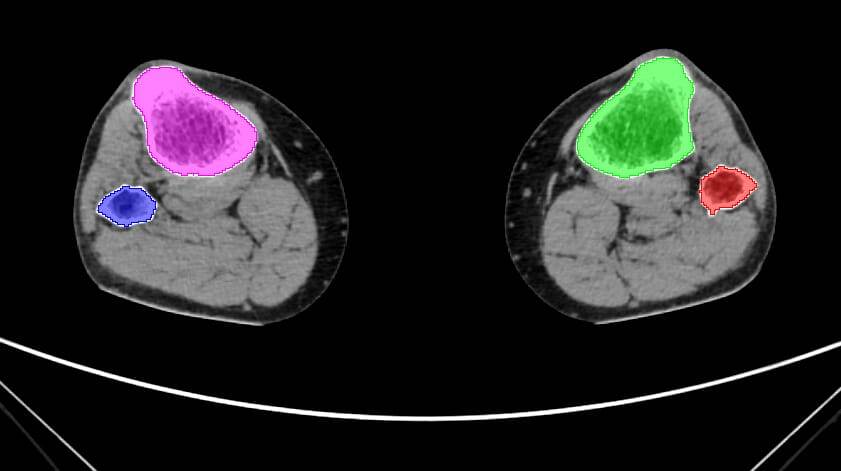

Ученые КГУ обучили нейросеть выделять кость из других тканей на каждом срезе компьютерной томографии:

— Нам, людям, кажется, что это несложно, но заставить нейросеть решать данную задачу не так просто. Нейросеть учат, показывая ей тысячи размеченных срезовКТ. Это колоссальный труд: мы в полуручном режиме разметили порядка 5 тысяч срезов, «покрасив» каждый пиксель, относящийся к кости, — рассказывает Олег Черепанов.

Такая задача в машинном обучении называется семантической сегментацией.

После долгого процесса обучения был получен результат — одна из нейронных сетей может с точностью 98% находить все пиксели кости на новых снимках КТ, затрачивая на операцию менее минуты.

Результаты семантической сегментации снимков КТ открывают дорогу к 3D-реконструкции костей и проектированию персонифицированных имплантатов.